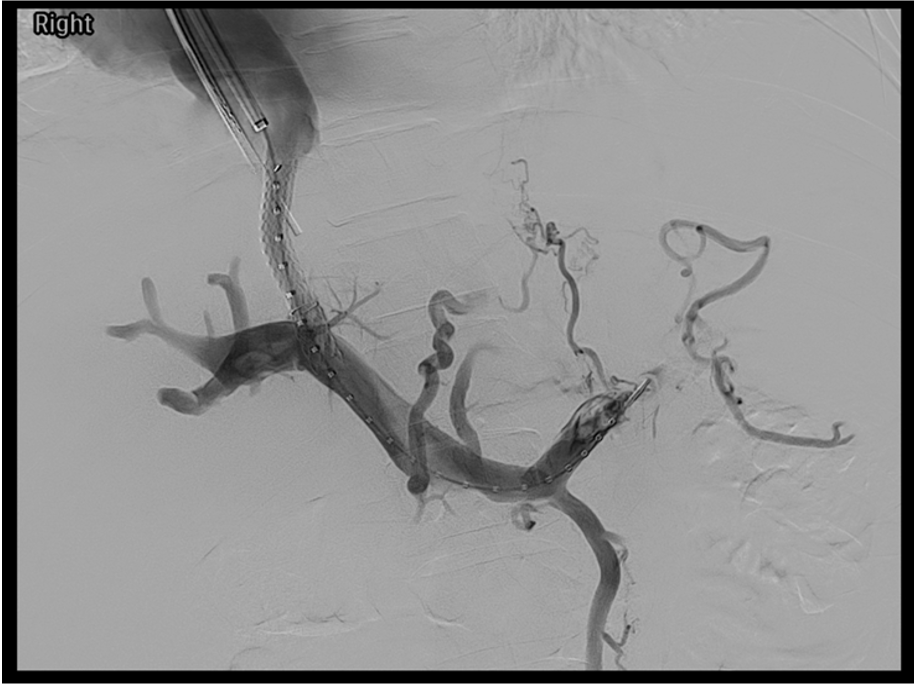

- Portal vein access — advance the TIPS needle set into the hepatic vein; puncture from hepatic vein into the portal vein under imaging guidance (fluoroscopy alone, or with intracardiac echocardiography for real-time visualization); confirm intraportal position by aspiration and small contrast injection showing portal branching

- Wire and sheath placement — advance wire into the portal system; upsize to working wire and sheath; perform portal venography and measure direct portal pressure

- Covered stent deployment — advance the ePTFE-covered stent (Viatorr); the covered portion spans the liver parenchyma and uncovered portion extends 1–2 cm into the portal vein

- Post-dilation and final assessment — dilate deployed stent; repeat pressure measurements and portal venogram; embolize varices if indicated; document final PPG